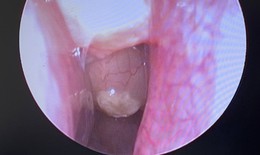

Bé 6 tuổi tím tái sau khi ăn phô mai, bác sĩ phát hiện mắc bệnh hiếm gặp

Camera bệnh viện - 01/10/2025 16:02SKĐS - Bé trai 6 tuổi ở Huế tím tái, lịm người sau khi ăn phô mai. Khi đến bệnh viện, bác sĩ phát hiện trẻ mắc dị dạng mạch máu hiếm gặp, có thể gây nguy hiểm tính mạng nếu không được can thiệp kịp thời.